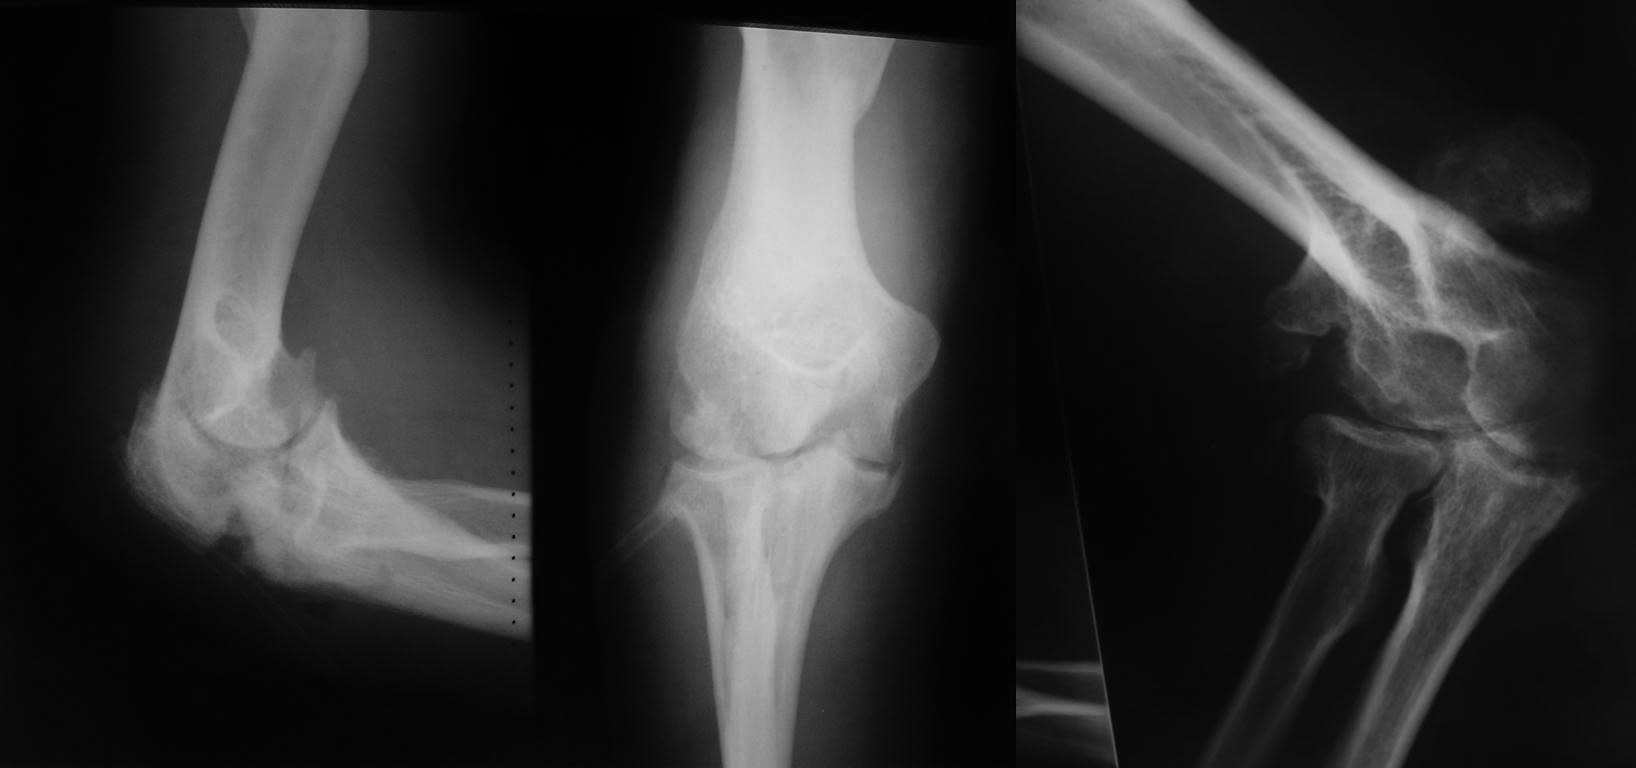

Ложный сустав локтевой кости на фоне посттравматического артроза |

Пациент 45 лет. Обратился по поводу ложного сустава левого локтевого отростка. Травма - падение с высоты - в 2002 г. (перелом левой плечевой кости в средней трети и перелом локтевого отростка). Плечевая кость срослась самостоятельно с небольшим угловым смещением. Локтевой отросток прооперирован по Веберу. В 2003 г. обратился ко мне с картиной выраженной тугоподвижности, гнойного артрита левого локтевого сустава и ложного сустава левого локтевого отростка. Были удалены фиксаторы, сустав дренирован. Через 3 дня, после стихания явлений острого воспаления, выполнены артротомия локтевого сустава путем разъединения отломков локтевого отростка; удалены остеофиты и гетеротопические оссификаты, окружавшие локтевой сустав, выполнен артролиз (первые 2 снимка). Послеоперационная рана зажила первичным натяжением, объем движений в локтевом суставе резко увеличился. Тогда на повторную операцию пациент не решился. Решился вот уже столько лет спустя: "Сильно располнел и даже лампочку вкрутить невозможно" (третий снимок). Объем движений в локтевом суставе практически полный. Естественно, без активного разгибания. Движения безболезненны. Вопрос: какую тактику Вы бы посоветовали в данной ситуации?